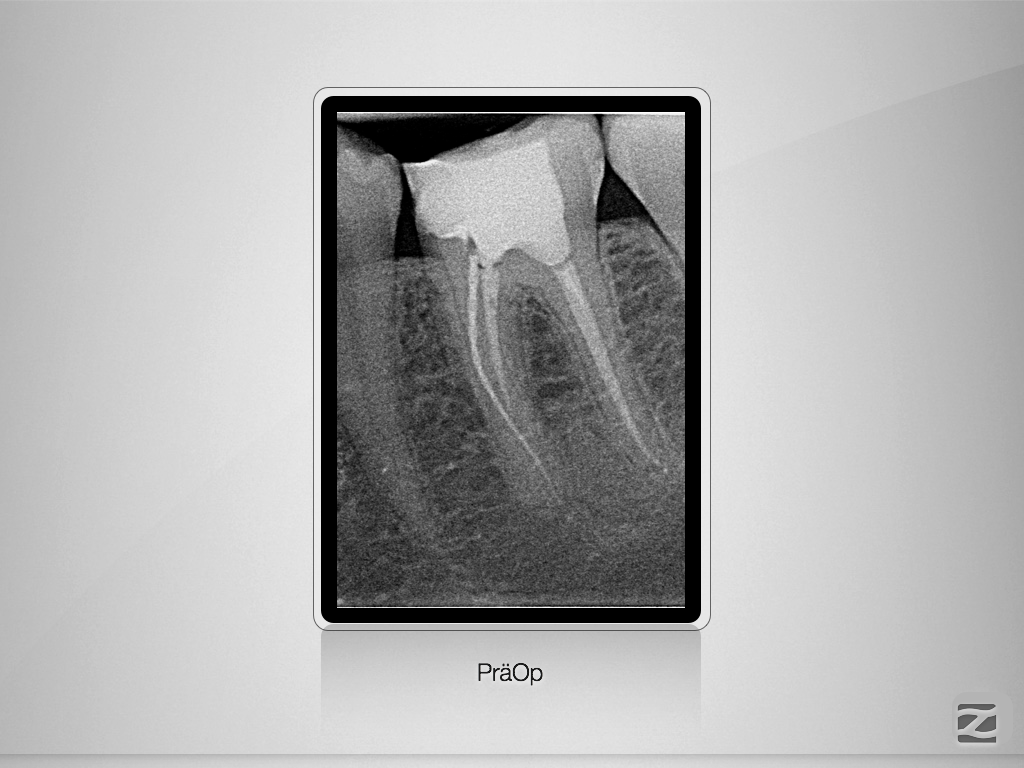

36D.001

1024 × 768

Fraktur auf voller Arbeitslänge